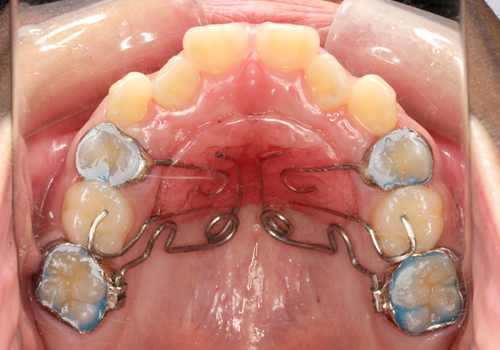

症例08. ペンデュラム

パラタルパッドと上顎小臼歯を固定源として上顎大臼歯を遠心移動させる装置。

取り外しできませんが、毎回Drが調整します。

| 治療内容 | 1:上顎大臼歯をワイヤーの弾性力で遠心へ送る 2:スペースが生まれているのが確認できる 3:スペースを使って前歯の凸凹を並べる |

|---|---|

| 期間 | 半年~2年 |

| 費用 | 300,000円+税 |

| リスク | 磨きづらい箇所は虫歯になるリスクが あります。 |